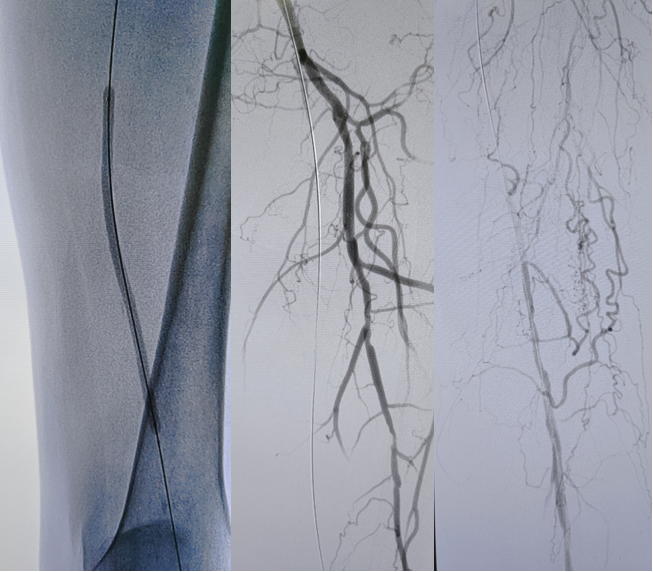

病例2(股腘动脉长段闭塞):

另一例长段闭塞病变,IVUS证实导丝真腔通过后,指导术者选择了合适尺寸的Rotarex导管进行减容,联合普通球囊(POBA)预扩及DCB治疗,获得了满意的管腔,避免了支架植入。

图:多处假腔通过,遂5mm球囊预扩

图:一期支架植入